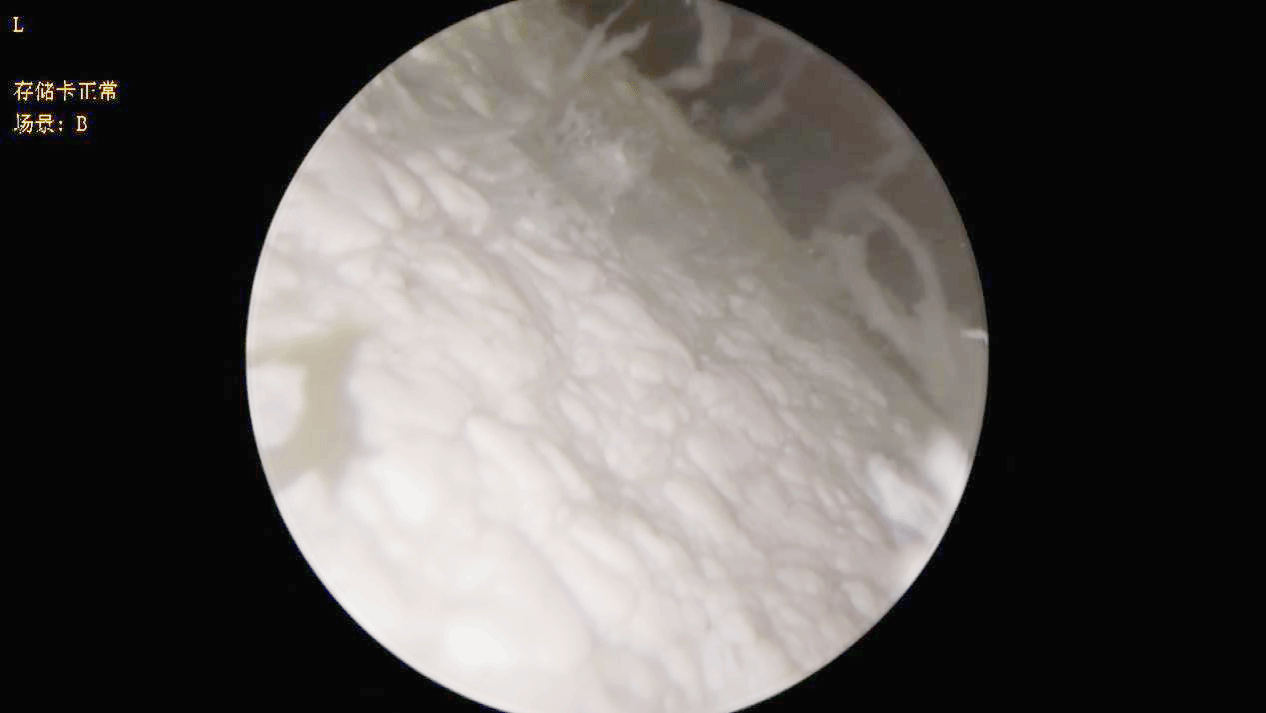

11月18日,在手术室全力配合、学科带头人肖长虹全程指导下,由主治医师罗贵湖主刀,主治医师钟汉协助,为何伯施行局麻下右膝关节针刀镜清理术。术中见到关节滑膜、软骨表面大量白色尿酸结晶,软骨大片脱落,滑膜绒毛增生充血。关节灌洗液呈牛奶色,经1500毫升生理盐水灌洗后灌洗液开始变得澄清,可见细颗粒状的痛风石随液体排出。手术历时30分钟,出血仅约2ml。